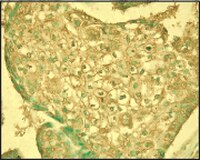

| Positive control | Breast carcinoma tissue |